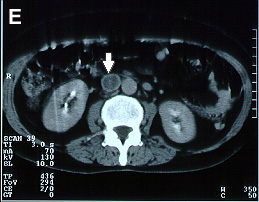

Imagens tomográficas da paciente após a trombose da veia cava inferior. Nota-se a sequência de A para E em que se vê a veia cava normal ao nível das veias renais e abaixo do clipe a veia cava trombosada (aumento do volume com forma circular e halo com captação de contraste)